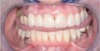

Prothèse amovible complète

Prothèse amovible complète avec polychromie

Prothèse Adjointe Complète